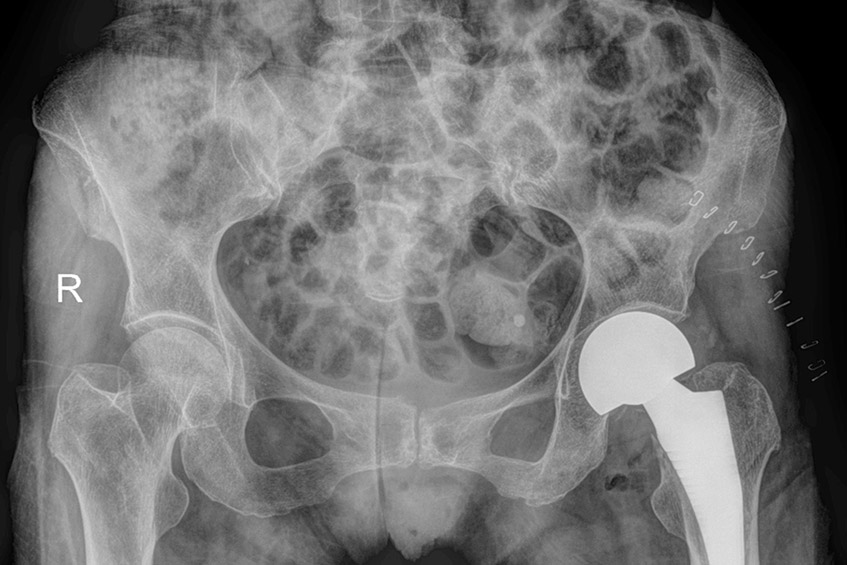

ThS.BS.CKI Đặng Khoa Học (BVĐK Tâm Anh) trực tiếp khám cho cụ Hạnh cho biết, cụ bị gãy kín cổ xương đùi trái phân loại Garden IV, di lệch nhiều, tuy nhiên không thể áp dụng cấp cứu nắn lại các di lệch và kết hợp xương bằng vít hoặc một loại nẹp đặc biệt DHS kèm vít như cho người trẻ tuổi. Người bệnh lớn tuổi đều đã bị loãng xương nên mật độ xương kém, nếu gãy cổ xương đùi di lệch nhiều, thay khớp háng là lựa chọn an toàn và mang lại hiệu quả cao nhất. Bởi nếu nắn lại phần xương gãy thì sau đó chỏm xương đùi vẫn sẽ hoại tử, do không còn được cấp máu nuôi dưỡng. Bác sĩ quyết định phẫu thuật thay khớp háng bán phần để cụ có thể đi lại ngay và tránh được những biến chứng kể trên.

Việc thay khớp háng bán phần tại BVĐK Tâm Anh hiện nay được thực hiện bằng kỹ thuật Superpath. Kỹ thuật này không xâm lấn nhiều đến cơ, vết mổ chỉ dài 5cm, không cắt cơ và bao khớp sau. Bệnh nhân mất rất ít máu, giảm đau tối đa, bảo tồn tối đa các cấu trúc cơ khớp, tránh trật khớp. Song song, bác sĩ cũng sử dụng phương pháp giảm đau đa mô thức kết hợp phục hồi chức năng ngay sau phẫu thuật.